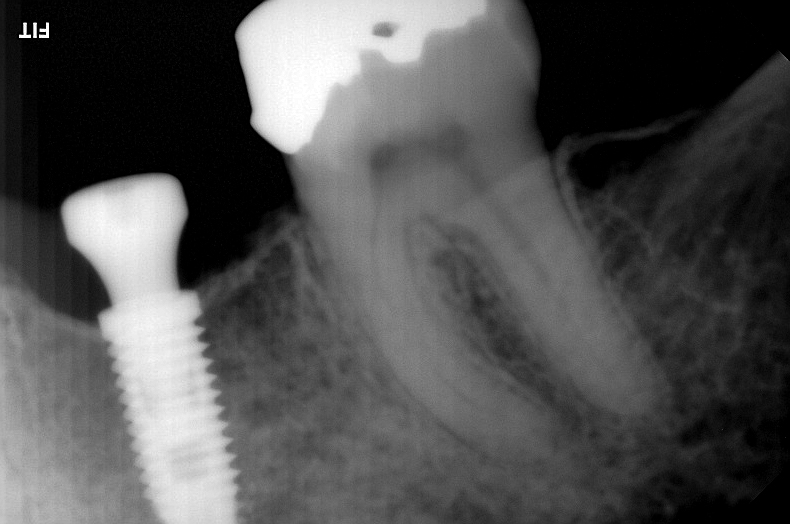

Perda óssea avançada

Quando a perda óssea já está avançada por conta de doenças bucais como a gengivite, periodontite e outros problemas, é preciso avaliar se o implante imediato ainda pode ser realizado. Caso o quadro seja favorável, associa-se o implante imediato à técnica de enxerto ósseo e/ou conjuntivo em uma mesma cirurgia, com o objetivo de regenerar o osso e garantir a estabilidade do implante.